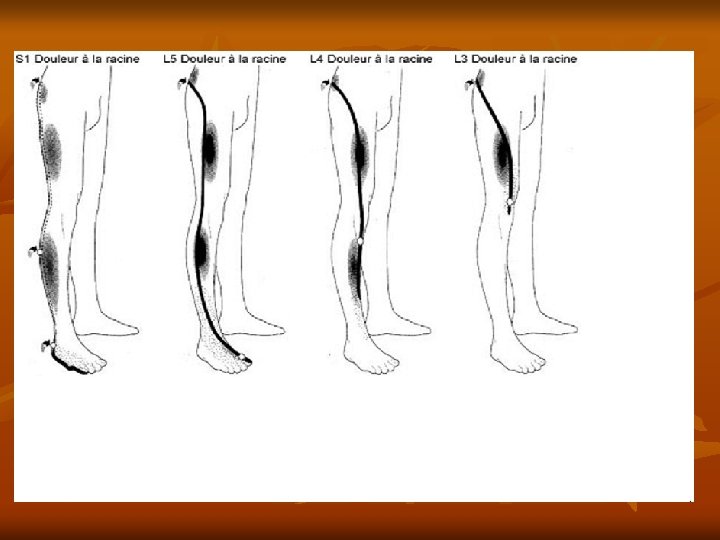

Définition Douleur irradiant le long du trajet sciatique et/ou ses racines. Le nerf sciatique naît de la réunion de deux racines issues de la moelle épinière, L 5 et S 1. Il descend verticalement à la face postérieure de la cuisse avant de se diviser au creux poplité en nerf sciatique interne et en nerf sciatique externe.

Causes C’est une compression des racines nerveuses L 5 ou S 1 due à une hernie discale (extrusion du disque intervertébral dans le canal médullaire), se manifestant par : • La lombalgie • La radiculalgie (douleur liée à la compression de la racine) la sciatique : L 5 face externe de la jambe S 1 face postérieure de la jambe la cruralgie : L 3 -L 4 partie antérieure de la cuisse